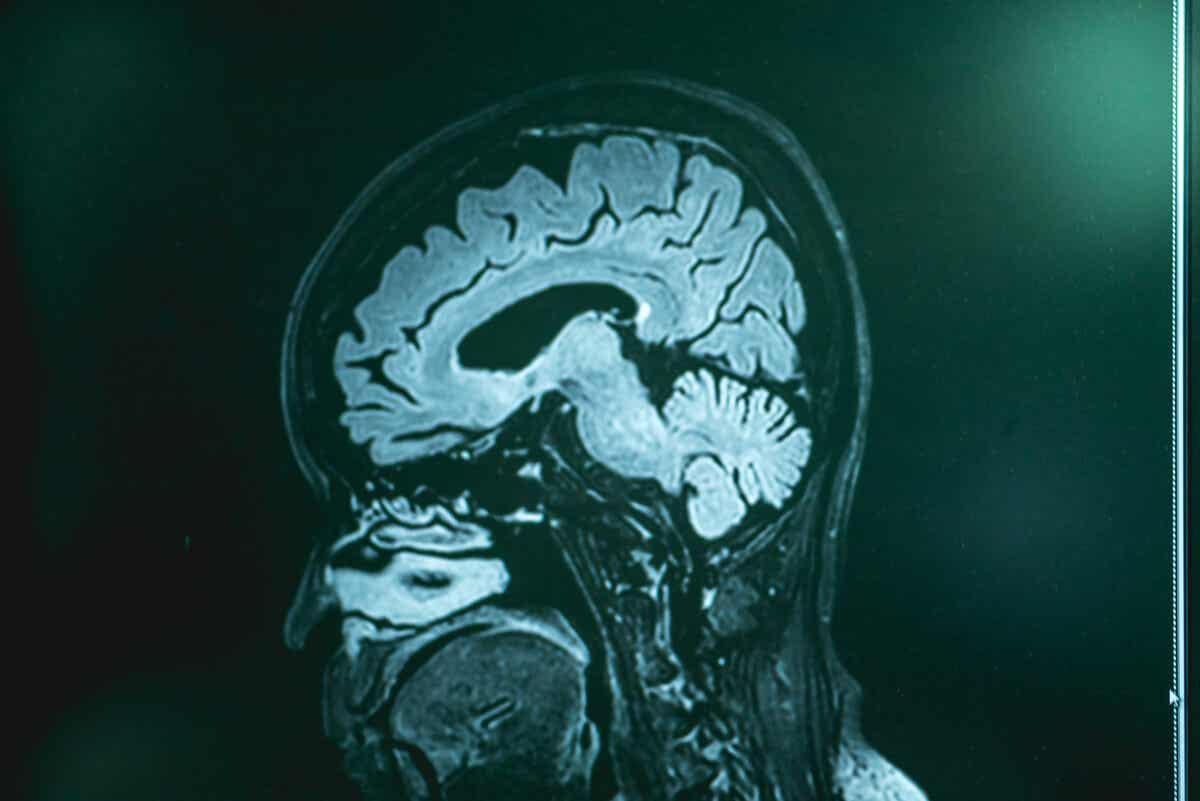

On the other hand, imaging tests (computed tomography and magnetic resonance imaging) don’t detect the disease but can rule out other possible health issues. Once the cerebrospinal fluid has been obtained, doctors perform cultures or genetic analyses in search of the amoeba genome.